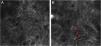

The melanocytes in the Dermal-Epidermal Junction (DEJ) are not usually identifiable in normal skin from individuals with phototype I‒II skin. The DEJ with RCM is characterized by bright basal keratinocytes surrounding dark dermal papilla, creating a pattern known as edged papillae, formed by well-demarcated papillary rings around a dark center (Fig. 4).

RCM of the Dermal-Epidermal Junction (DEJ). (A and B) Edge papillae formed by well demarcated papillary rings around a dark center representing the pigmented keratinocytes and/or basal melanocytes surrounding dark dermal papilla. The ringed pattern forms the edge papillae. (C) Histologically, the ringed pattern represents elongated rete-ridges with an increased number of single melanocytes at the basal layer.

Pigmented melanocytic lesions can present with two patterns at the DEJ: the ringed pattern, characterized by a rim of bright cells forming the edged papillae (Fig. 4); and the meshwork pattern, characterized by elongated cords and junctional thickening (Fig. 5). Histologically, the ringed pattern represents elongated rete-ridges with an increased number of single melanocytes at the basal layer. The pigmented basal keratinocytes correspond to a lentiginous pattern. In contrast, the meshwork pattern corresponds in histopathology to the enlargement of the interpapillary space formed by aggregated melanocytes, with predominantly small, non-confluent nests at the tip of the rete ridges.

RCM of the Dermal-Epidermal Junction (DEJ). (A) Meshwork pattern, characterized by elongated hyper-reflective cords, corresponding the junctional thickening. (B) Higher magnifications showing enlongated cords interconnecting, round white structures represent the milia-like cysts (red arrows). (C) Histopathology showing the enlargement of the interpapillary space, formed by aggregated melanocytes, with predominantly small, interconnecting nests at the tip of the rete ridges.